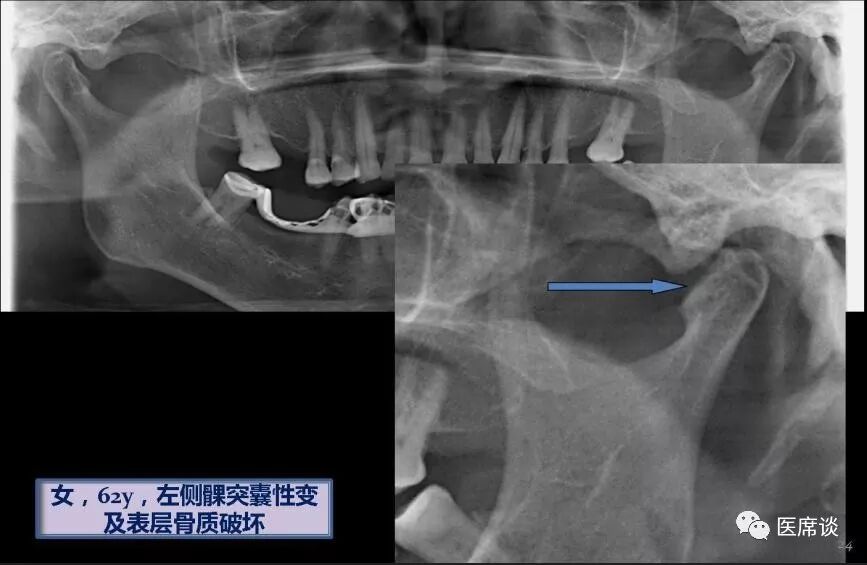

具体病例: ,患者女性,62岁,从曲断上看左侧关节髁突有囊性变,骨质不

图片尺寸867x565